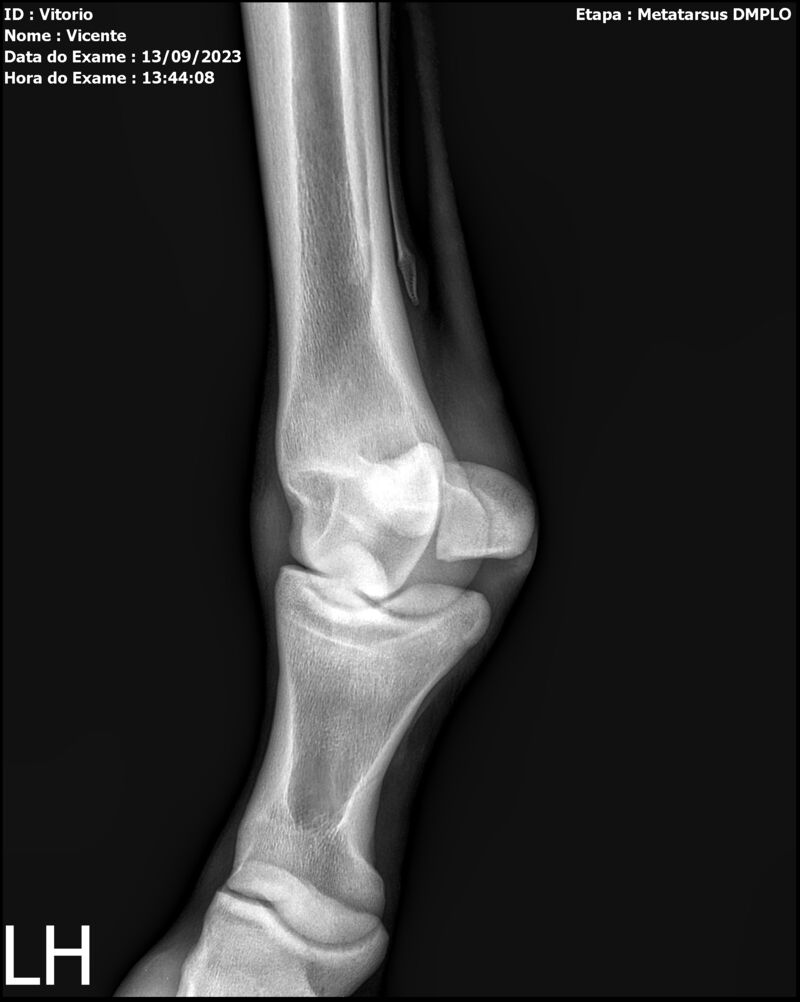

THUNDER ZC

Raça: BRASILEIRO DE HIPISMO

Sexo: MACHO - POTRO

Nascimento: 17/09/2022

Altura Aproximada: 1,54

Pel.: CASTANHO

Registro: EM AND

Vend.: VICENTE CONTE

Local : PORTO FELIZ/SP